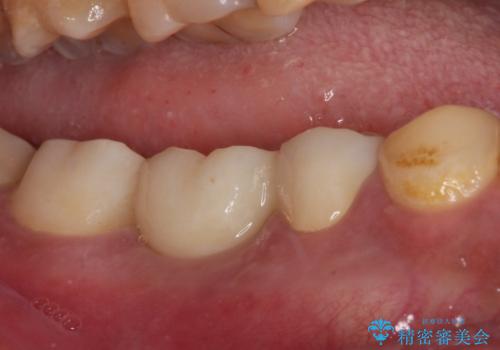

抜歯部分の治癒を待つ間に、全体的な汚れの多さを改善する指導と処置を進め、その後オールセラミックブリッジにて補綴治療を行うこととしました。

神経を取り除く可能性のあった奥歯ですが、何とか保存することができました。

奥歯はしっかりと治療することができたので、今後は虫歯予防と他の要治療歯の処置を行っていくことになります。